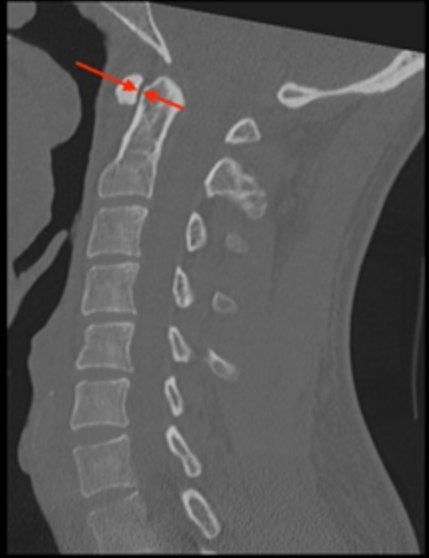

The distance between the anterior arch of C1 (atlas) and the odontoid process (dens) of C2. It reflects the integrity of the transverse atlantal ligament, which restrains anterior translation of C1 on C2.

• Use a midsagittal CT reconstruction.

• Identify the posterior cortex of the anterior arch of C1 and the anterior cortex of the dens.

• Measure the shortest distance between these two structures at the midportion of the dens.